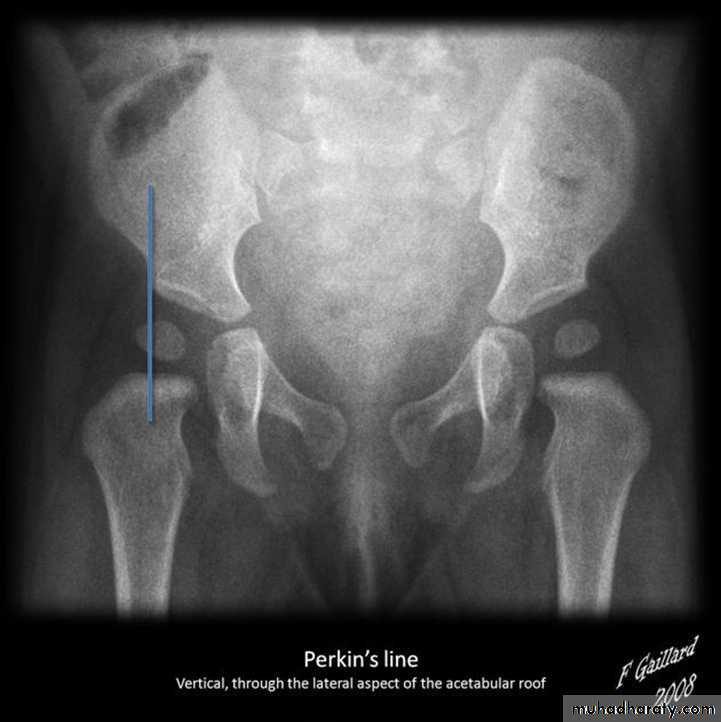

Who can you do Von Rosen view

At 3-6 months :abduction of the thigh 45 degree and internal rotation

Shenton line is drawn along the inferior border of the superior pubic ramus and should continue laterally along the infero medial aspect of the proximal femur as a smooth line. If there is supero lateral migration of the proximal femur due to DDH then this line will be discontinuousPerkin line is drawn intersecting the lateral most aspect of the acetabuler roof & iliac creast

Q…CDH occurs most commonly in ????(70%) in the left hip . Bilateral involvement is seen in 5%

Q…By simple diagram draw pelvis with lines (shenton’s & Perkins line)